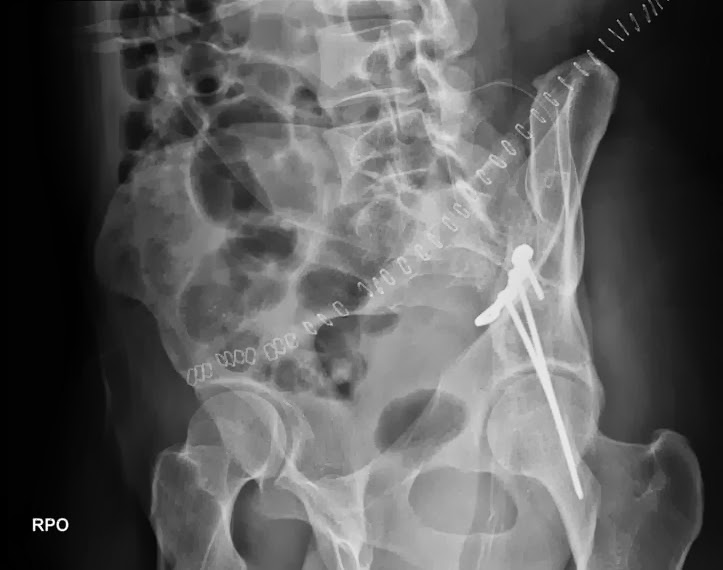

I'm about a year behind with art posts. Just lazy? Preoccupied perhaps, with life and other "priorities"? Well maybe, but mostly I just got hit really hard in the hip by a speeding car. This is old news to many of you but, in case you didn't know I got the bumper kiss of death back in May of 2011. Since that time I have been making a slow recovery back to mostly normal heath. Wheelchairs, walkers, canes, you name it. I spent about a month in the hospital, including a very invasive surgery which implanted 3 long titanium snakes in my hip. Here's some photos including the incision, a couple X-rays of my new metallic accessories and the car I was in when I got T-boned. Incidentally the jaws of life couldn't' get my car open so the fire department had to saw off the entire roof of my cute little Toyota Cellica (see below)... Any-who it's great to be back! Thank you very kindly for all your thoughts, prayers, and encouragement during my ongoing recovery process. And...Look for new and somewhat regular art post from me for a while to come. =)